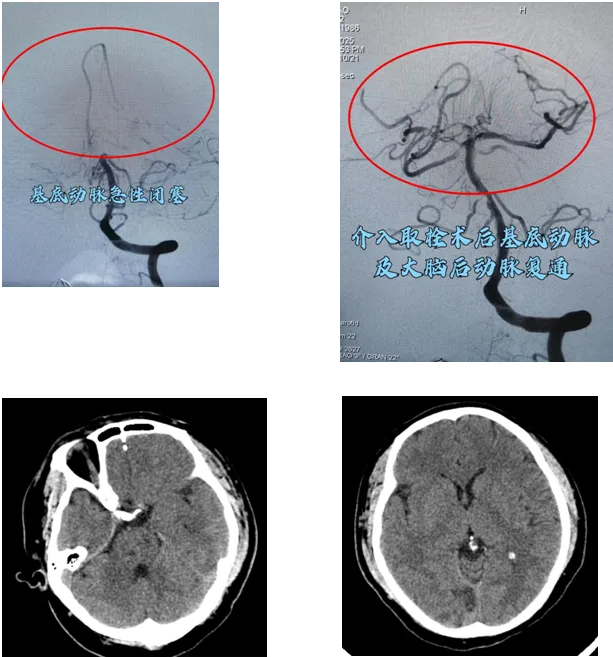

在导管室、麻醉科等科室的默契配合下,神经外科三病区负责人马建副主任医师、周少龙副主任医师凭借精湛的技术和丰富的经验,判断基底动脉闭塞为此次病变的责任血管,通过介入技术成功开通了闭塞的基底动脉,实现了血管的再通。

QQ截图20250111091543

▲ 术后复查CT,患者颅内未见出血